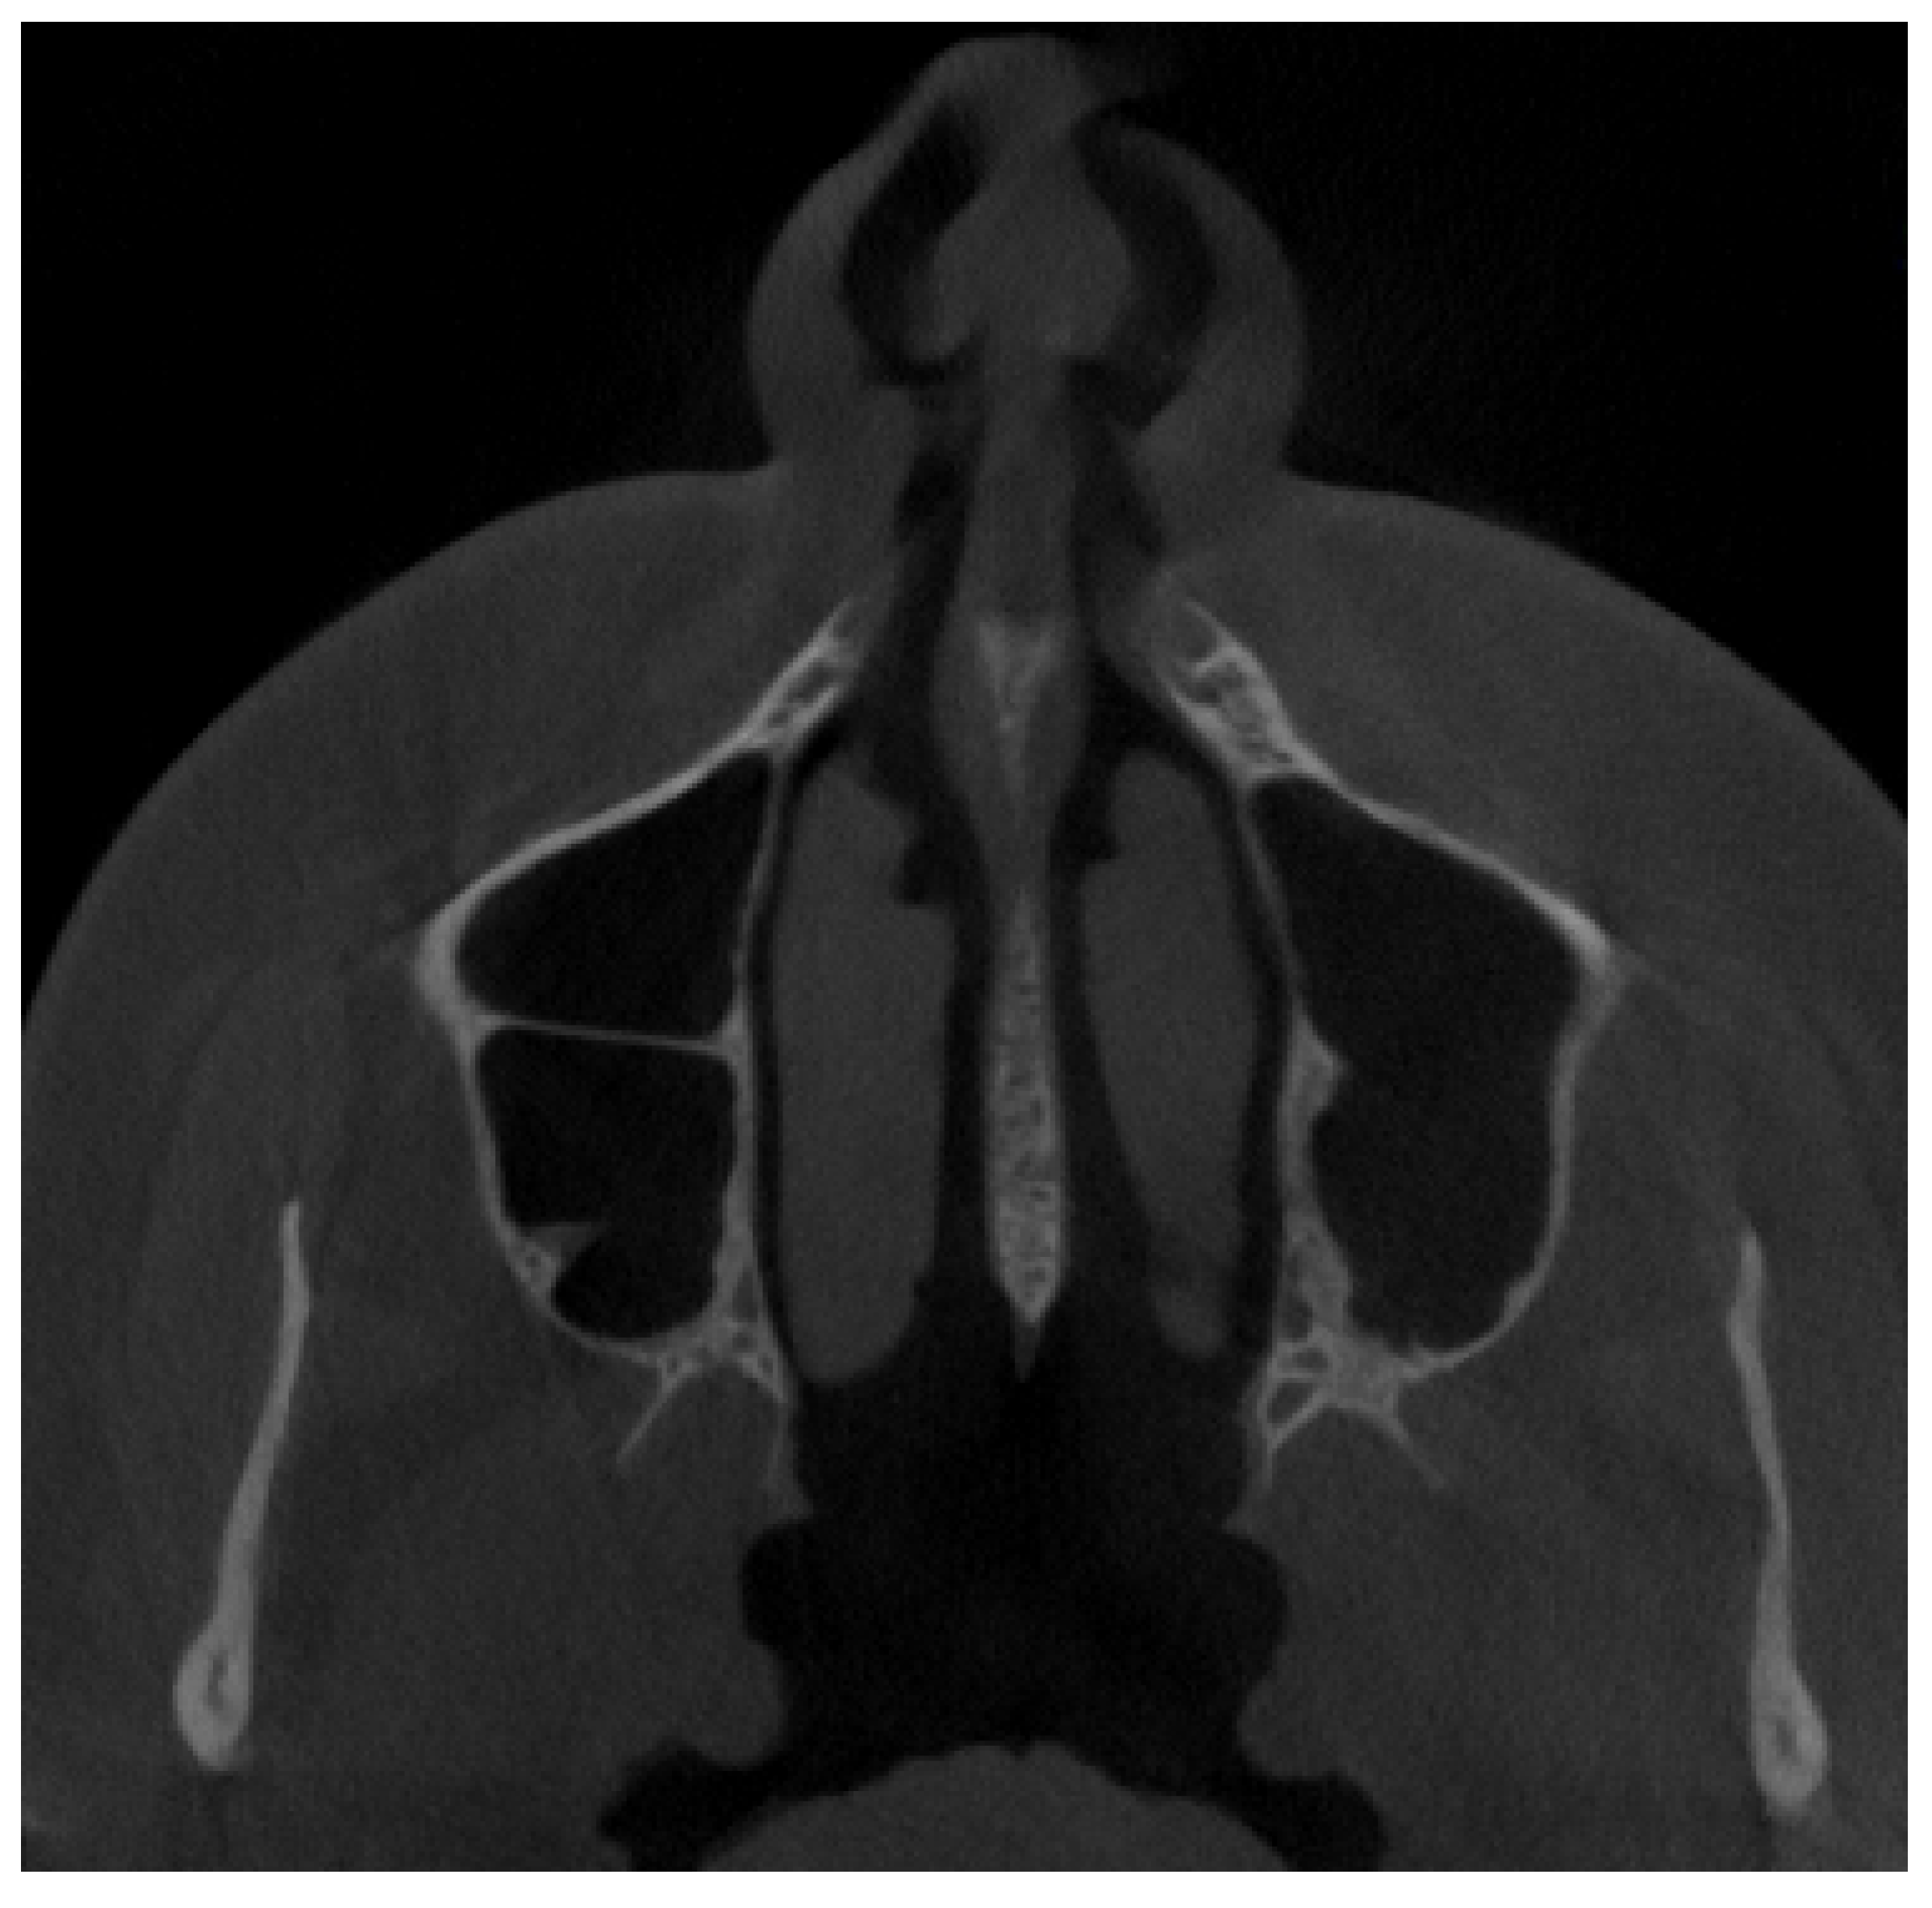

2. Material and Methods

2.2. Cone Beam Computed Tomography Characteristics

2.3. Methods—Classification Proposal